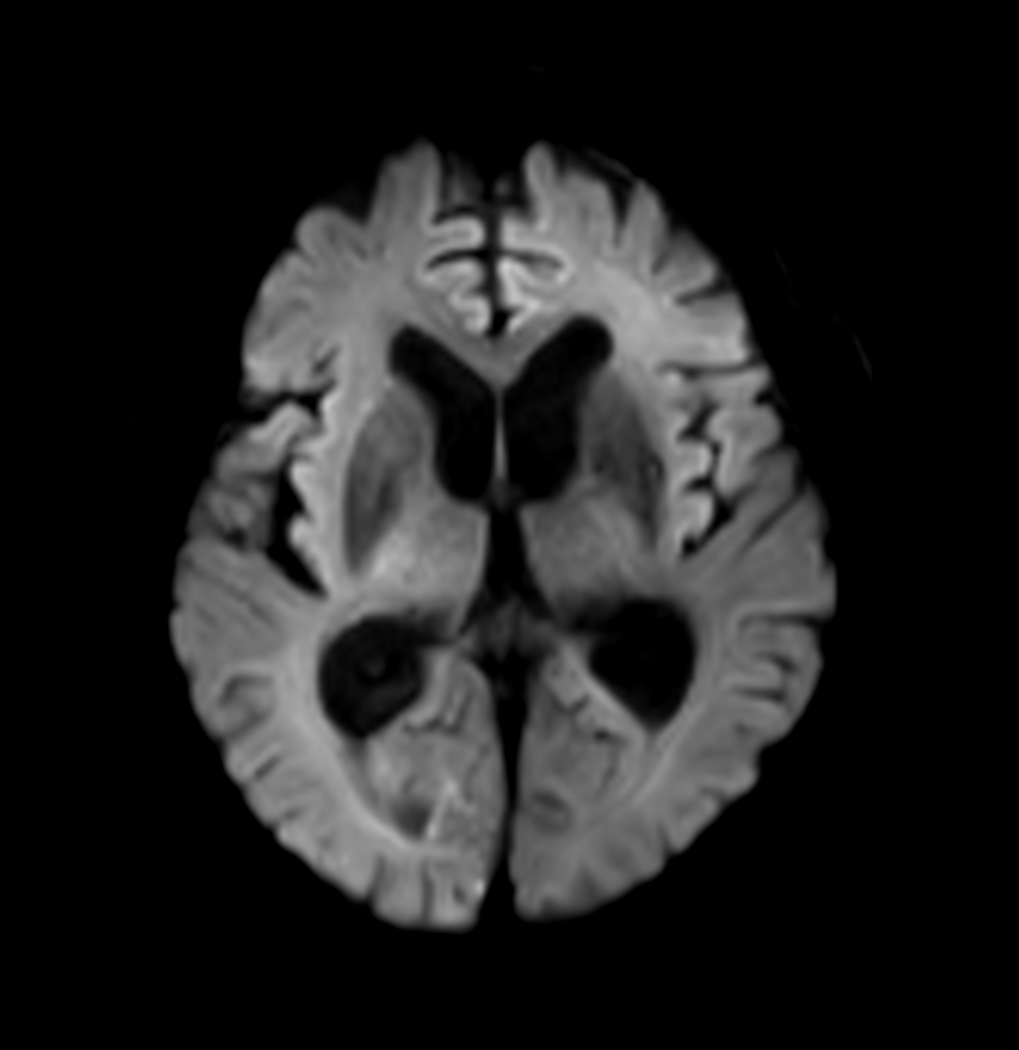

DWI (b2000)